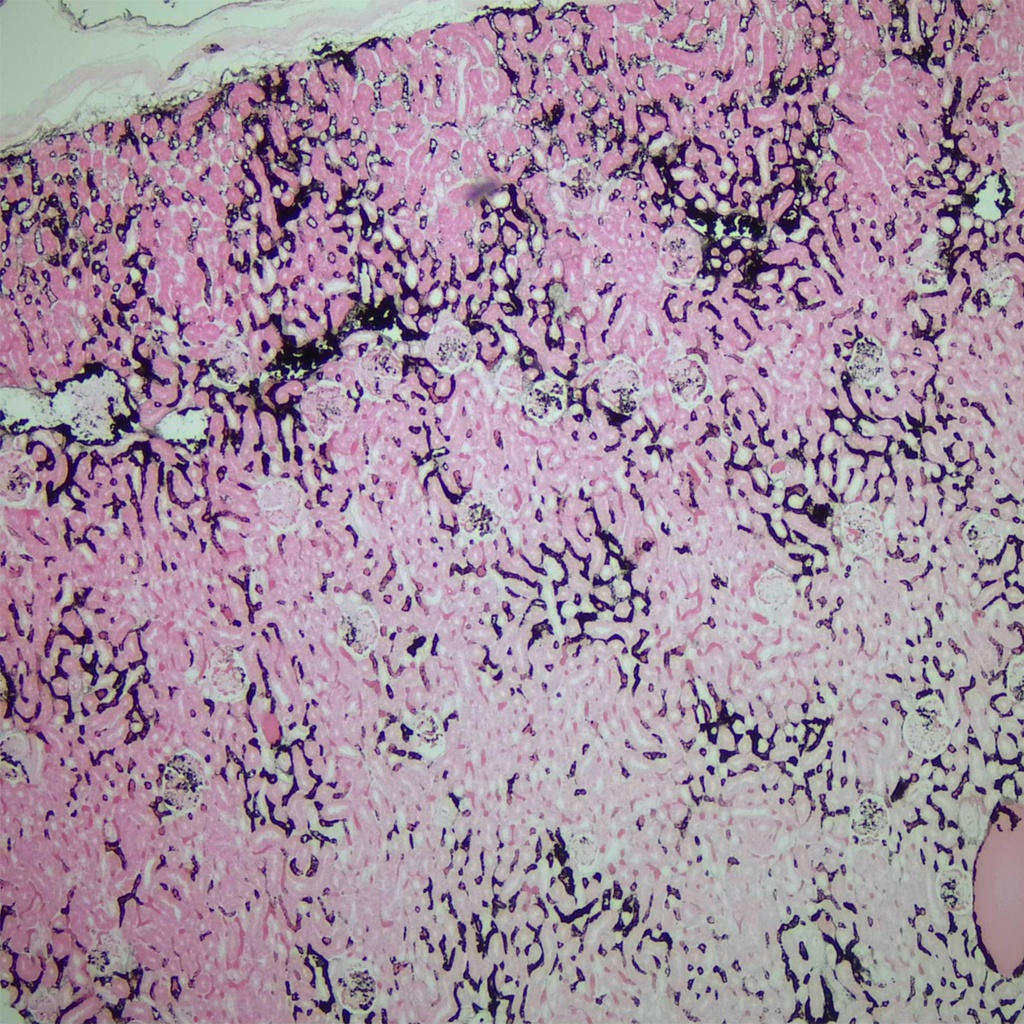

Seccion de riñón de conejo